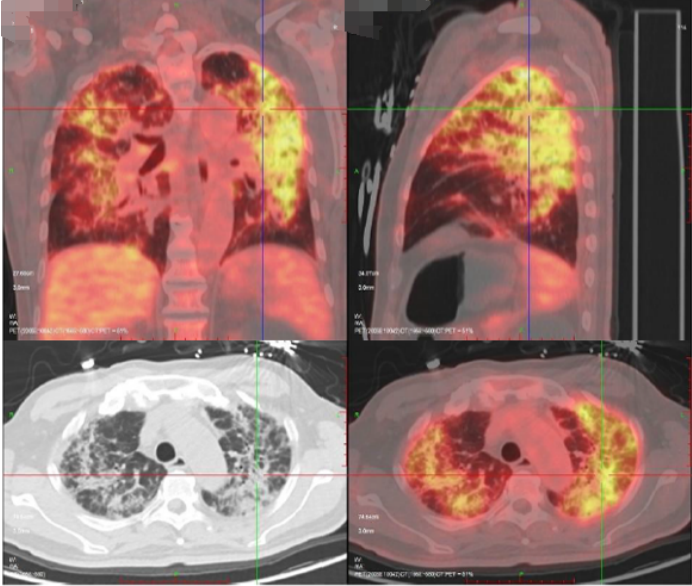

患者既往前列腺癌病史,双肺弥漫间质性病变,考虑肿瘤不能除外,遂于4月15日进一步行PET-CT(图4),结果显示:双肺多发病变,纵隔及双肺门淋巴结代谢增高,考虑炎症。前列腺代谢不均匀增高,符合前列腺癌表现。左侧耻骨及双侧坐骨骨质异常伴代谢增高,考虑转移。患者双肺病变较前快速进展(图5)

图4  患者PET-CT(2023-04-15)